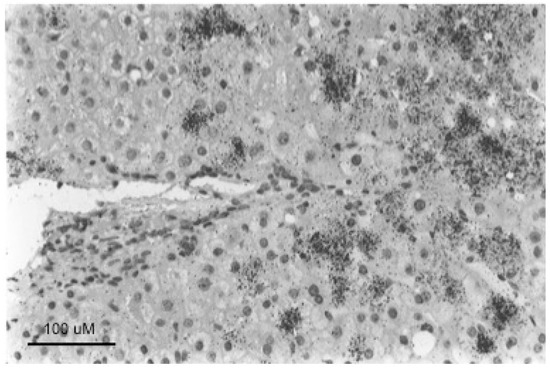

Well-defined foci of hepatocytes, negative for HBV replication, as assessed by HBcAg staining of tissue sections, have also been observed in chronically HBV-infected chimpanzees [11]. We are not aware of reports of such foci in human livers, where the number of productively infected hepatocytes in late stages of chronic infection may be too low to show well-defined foci of HBV-negative cells, as illustrated in Figure 5. In any case, while it seems likely that woodchuck FAH are clonal, an obvious question is whether foci of virus-negative but normal appearing hepatocytes as seen in HBV-infected chimpanzees and WHV-infected woodchucks are also clonal, or have another explanation, such as highly localized immune clearance and control. At present, the only point that has been addressed, using sections of HBV-infected human liver, is that hepatocyte clones can be made up of normal appearing and focally accumulated hepatocytes [10,74]. In these examples, clonality was recognized by end-point dilution of liver DNA extracted from histological tissue sections followed by inverse-nested PCR to detect virus-cell junctions. Unfortunately, these samples lacked the well-defined foci of virus-negative hepatocytes seen in woodchucks and chimpanzees that might have allowed a positive correlation between clonal expansion of hepatocytes and the loss of virus production.

Figure 5.

In situ hybridization detection of cytoplasmic HBV DNA, a marker of productive HBV infection in a patient with mild hepatitis and developing cirrhosis. Hepatocytes containing high-levels of HBV DNA were distributed randomly and in periportal regions of the lobule. Many hepatocytes with undetectable levels of HBV DNA were also observed. HBV DNA was detected by in situ hybridization with an 125I-labelled HBV DNA probe followed by autoradiography for 168 h and staining with hematoxylin and eosin (H&E). Figure adapted and reproduced with permission from reference [95], Mason et al., Hepatology International, published by Springer, 2007.

In summary, assuming that all hepatocytes contribute to liver homeostasis in normal liver (Model 4) leads to the conclusion that the largest hepatocyte clones that emerge during chronic HBV infection must have a growth and/or survival advantage over most other hepatocytes (Figure 6), suggesting that in the case of chronic HBV infection Model 4 is not strictly true. Experimental observations with liver samples from HBV-infected humans (Figure 5) and chimpanzees and WHV-infected woodchucks (Figure 4) suggest that a shutdown of virus replication may contribute to clonal expansion of hepatocytes by providing a survival advantage over hepatocytes that continue to support the replication of HBV. This would occur even without a proliferation advantage for these hepatocytes.

The third major problem is the difficulty of correlating clonal expansion of hepatocytes with specific phenotypes that facilitate immune escape. While we favor the idea that loss of productive HBV infection, providing at least partial escape from the antiviral immune response, is a major facilitator of clonal expansion (Figure 4 and Figure 5), this is just an inference made from the various observations discussed earlier. Testing this idea is challenging because of the difficulty of acquiring suitable samples, with well-defined foci of, for instance, HBcAg-negative hepatocytes (cf., Figure 4), and with some lineage-specific marker of clonality such as integrated HBV DNA. While the woodchuck might be a suitable model, it is not clear if the frequency of integration of WHV DNA is high enough to make this practical. Clonal expansion of hepatocytes has been detected in WHV-infected woodchucks by end-point dilution inverse-nested PCR [99], but was only apparent in a few percent of hepatocytes by this assay. Clonal expansion of hepatocytes has been demonstrated using tissue sections of HBV-infected human liver originally cut for histologic analyses [10,74] but, as noted above, we are not aware of reports showing well-defined foci of HBcAg-negative hepatocytes. Thus, a more sophisticated approach may be needed, possibly using other genetic or epigenetic markers of clonality than integrated HBV DNA.